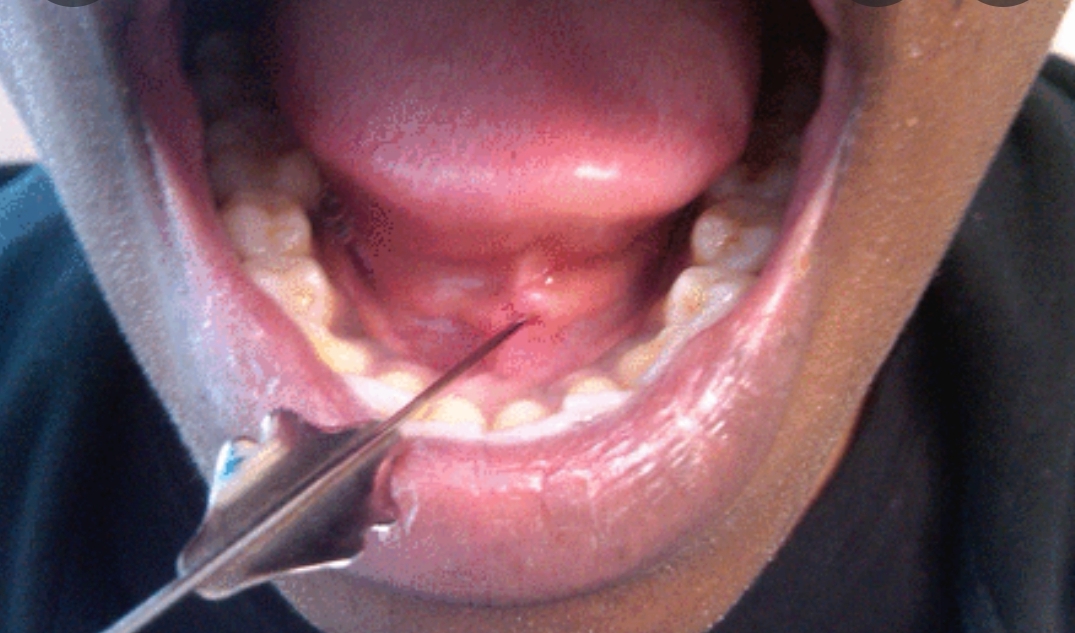

침샘염 증상

침샘염의 증상으로는 침샘 부위(귀밑이나 턱 밑)의 반복적인 부종과 통증, 발열이 있습니다. 특히 식사 시에 격렬한 통증이 유발됩니다.